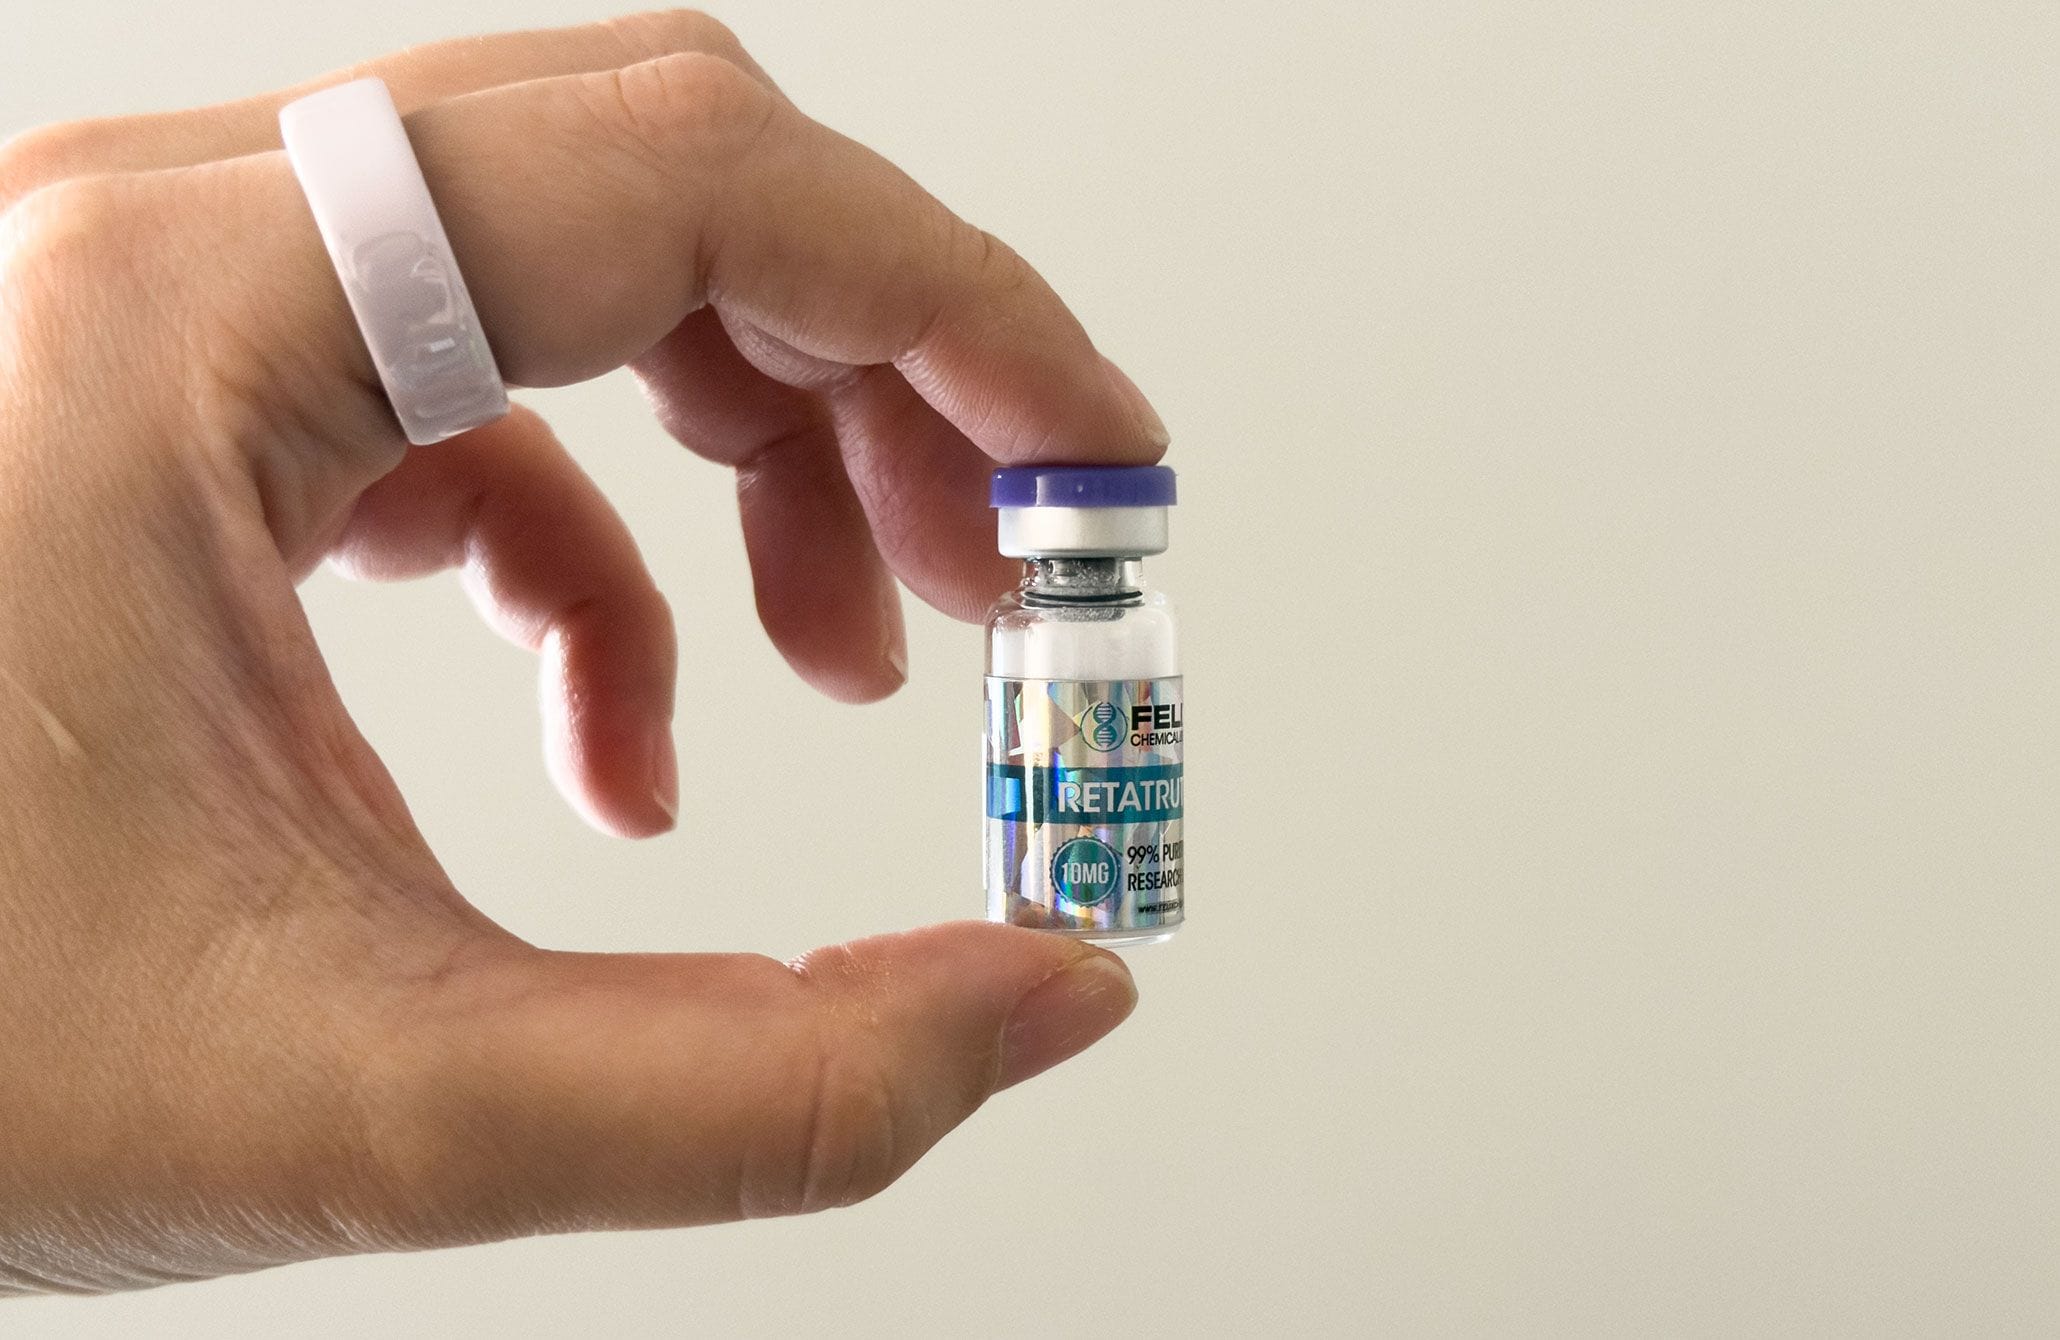

Read moreग्रे-मार्केट पेप्टाइड्स ने टिकटॉक में बाढ़ ला दी है क्योंकि फार्मासिस्टों ने सुरक्षा जोखिमों की चेतावनी दी है

टिकटोक के प्रभावशाली लोग रेटाट्रूटाइड की शीशियों की बिक्री कर रहे हैं – एक अस्वीकृत वजन घटाने वाली दवा जो ...